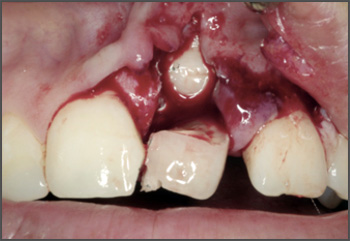

Surgery is needed to close the gap left by the cleft. This will usually happen when the child is under a year old.

Every cleft is unique, just like every child, so the exact treatment pathway will vary. It may include further surgery to help with issues such as speech and growth of adult teeth. It may also include speech therapy, help with hearing, orthodontic work, etc.